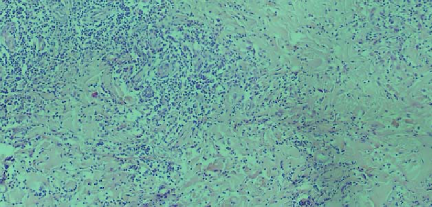

Leishmaniasis background and histology presentation. The World Health Organization (WHO) has selected cutaneous leishmaniasis as a neglected tropical disease (NTD) with growing, uncontrolled, and ignored infection affecting millions of people every year [14, 9]. It is unfortunately one of the world’s most neglected poverty-related diseases, affecting the poorest people in developing countries and it is associated with risk factors like malnutrition, immune system deficiency, migration, inadequate education, illiteracy, gender inequality, and a shortage of services [1]. Furthermore, only eight countries in the world contribute to 90% of leishmaniasis cases: Afghanistan, Algeria, Brazil, Iran, Pakistan, Peru, Saudi Arabia, and Syria [12]. It is a vector-borne infection caused by the protozoan parasite Leishmania. The vector is the female sand-fly. The lesions of cutaneous leishmaniasis vary in presentation ranging from a single self-limited skin lesion to multiple large destructive and ulcerated lesions on mostly the exposed parts of the body such as face, forearms, and lower legs [2]. Skin biopsy is considered the gold standard method for confirmation of diagnosis. The presence of large epitheloid granulomas and small hematoxylinophilic LD bodies (that are round, uniform in appearance, intracytoplasmic and sometimes distributed around the outer rim of the vacuoles) is critical for diagnosis and confirmation of leishmaniasis [4]. Large granulomas are visible at 10X but the smaller hematoxylinophilic bodies (around 3-4mm in size) are usually visible at 40X and can easily be missed if they are few in number, leading to misdiagnosis. Specialized dermatopathologists are the only ones who can diagnose these accurately based on patient history, clinical features, and laboratory diagnosis. It is thus critical to share the digitized slides of these cases from rural poor remote areas with dermatopathologists (mostly residing in urban centers) for quick diagnosis and accurate management of the patient.

Curated dataset. Skin biopsies from 12 patients diagnosed with cutaneous leishmaniasis (spanning the disease differentiation spectrum) were acquired from Agha Khan University with Internal Review Board approval # 2024-9038-28175. Six of these biopsies, stained with hematoxylin & eosin (H&E), were scanned using Huron’s TissueScope digital scanner at 40X. A cheap-yet-clinical grade ($200) microscope (BS-2020MD Digital Microscope from BestScope International Limited, China) with a built-in digital 1.3 megapixel CMOS USB camera and 1W 5-LED illumination with Halogen Lamp 6V/20W was then used to capture videos for all 12 skin biopsies at 10X resolution. To show generalizability of our whole-slide image creation workflow for other common pathologies beyond cutaneous leishmaniasis, we also acquired videos for core biopsies of breast, liver, duodenum, stomach, and lymph node.

We demonstrate our WSI creation workflow on Leishmaniasis cases, as shown in Figures 1 and 4. An expert pathologist reviewed the cases and annotated granulomas as well as LD bodies on the stitched images and our generated images in Figure 4. To show generalizability of our approach, we also show results on core biopsies of breast, duodenum, stomach, liver, and lymph nodes (Figure 5).